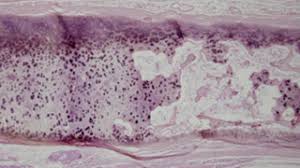

Click vào ảnh để xem 4 hình ảnh minh họa